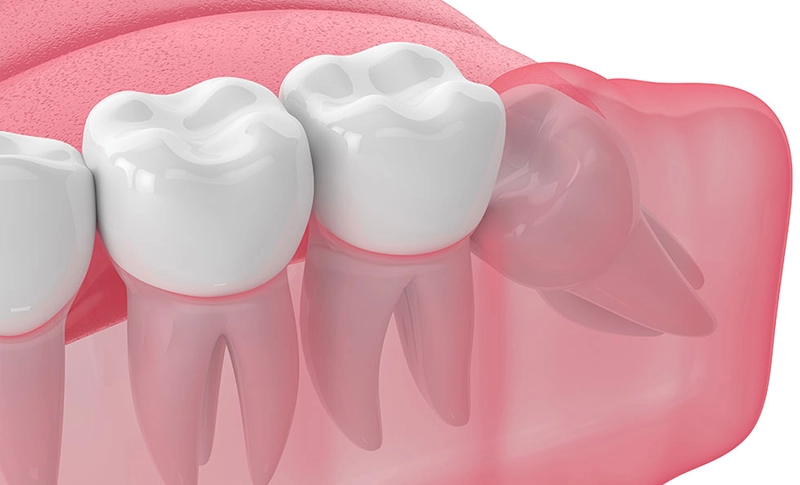

その結果、斜めに生えたり、一部だけ歯ぐきから顔を出したり、歯ぐきや骨の中に埋まったままになることがあります。

このような状態では、歯ぐきの腫れや痛み、隣の歯のむし歯、かみ合わせへの影響などを引き起こす場合があります。